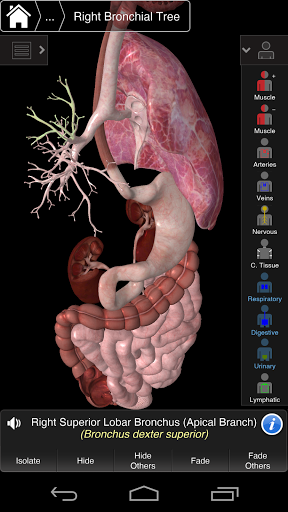

This app includes essential anatomy for 10 systems:

⁃Respiratory

⁃Digestive

⁃Urinary

⁃Lymphatic

Clever functionality found within the app allows the user to strip away layers of muscle via the ‘scalpel’ tool. This app provides users with the ability to turn on/off systems without the need to deselect individual structures or muddle through a multitude of predefined regional tabs, like other apps.

---- Multiple Selection Mode - Hide/Fade/Isolate individual or multiple structures

---- Correct audio pronunciation for every structure

---- Latin nomenclature for each anatomical structure